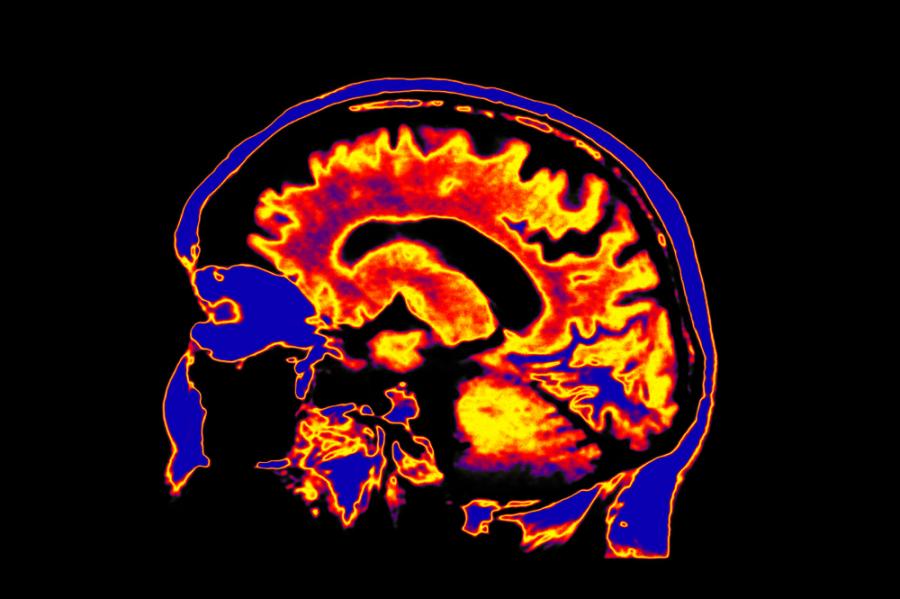

Депресията променя структурата на мозъка

Депресиите са широко разпространени състояния и точно през студените зимни месеци, когато денят е по-къс, много хора страдат от т.нар. сезонна депресия. Освен с тъжно настроение тя се характеризира с чувство на вътрешна празнота, както и с неспособност за вземане на решения, придружена от апатия и безнадеждност. Наред с психичните често възникват и соматични оплаквания като усещане за парализа, безсъние, безапетитие. Обикновено това състояние продължава до няколко седмици, но ако не се лекува, може да трае с години. Депресиите влияят не само върху психиката и субективните ни усещания; учените са доказали, че те могат да доведат до сериозни невроанатомични промени в мозъка.

Три участъка на мозъка играят съществена роля във връзка с депресията:

1. Хипоталамусът: Той е разположен близо до центъра на мозъка, съхранява спомените и регулира нивата на кортизола. Този стресов хормон се отделя най-вече когато тялото или психиката е под стрес, но също и при депресии. Ако въз основа на този химичен дисбаланс се освободят прекалено големи количества кортизол, това може да окаже трайно въздействие върху мозъка. Защото когато стойностите му са повишени, производството на мозъчни клетки може да се забави, в резултат на което се влошава способността за запомняне и се появяват проблеми с паметта.

2. Префронталната кора: Тя се намира в челната част на мозъка и отговаря за регулирането на чувствата, за вземането на решения, за спомените и за възпроизвеждането на преживявания. Също както при хипоталамуса, прекомерното отделяне на кортизол може да доведе до атрофия на предно-челната кора.

3. Амигдалата: Амигдалата – или бадемовидното тяло – отключва емоционални реакции като страх, радост или желание. При депресия увеличените нива на кортизола предизвикват повишена активност и уголемяване на бадемовидното тяло. Тази хиперактивност, с участието и на други участъци от мозъка, води до нарушение на ритъма сън/будно състояние. Прекалено активната амигдала може освен това да причини секретиране и на други хормони, което на свой ред създава хормонален дисбаланс.